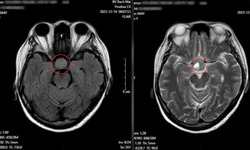

u tuyến yên

Phẫu thuật đồng thời hai đường mổ 'bóc' khối u tuyến yên đặc biệt hiếm gặp

Y tế - 08/04/2025 11:15SKĐS - Bệnh viện Hữu nghị Việt Đức cho biết các bác sĩ của bệnh viện vừa thực hiện thành công ca phẫu thuật phối hợp hai đường tiếp cận hiếm gặp cho trường hợp u tuyến yên kích thước lớn đã xâm lấn sâu, gây chèn ép nhiều cấu trúc quan trọng trong não...